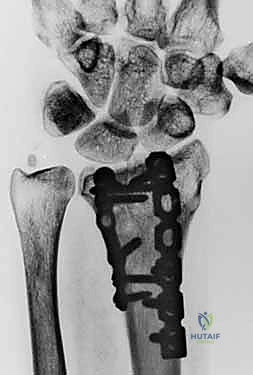

5. التثبيت بصفائح التيتانيوم (Internal Fixation)

للحفاظ على الوضع الجديد والمثالي للعظم، يتم استخدام صفائح تيتانيوم متقدمة ذاتية الغلق (Volar Locking Plates). هذه الصفائح مصممة تشريحياً لتلائم شكل الكعبرة، وتوفر تثبيتاً قوياً جداً يسمح للمريض ببدء تحريك أصابعه في اليوم التالي للعملية.